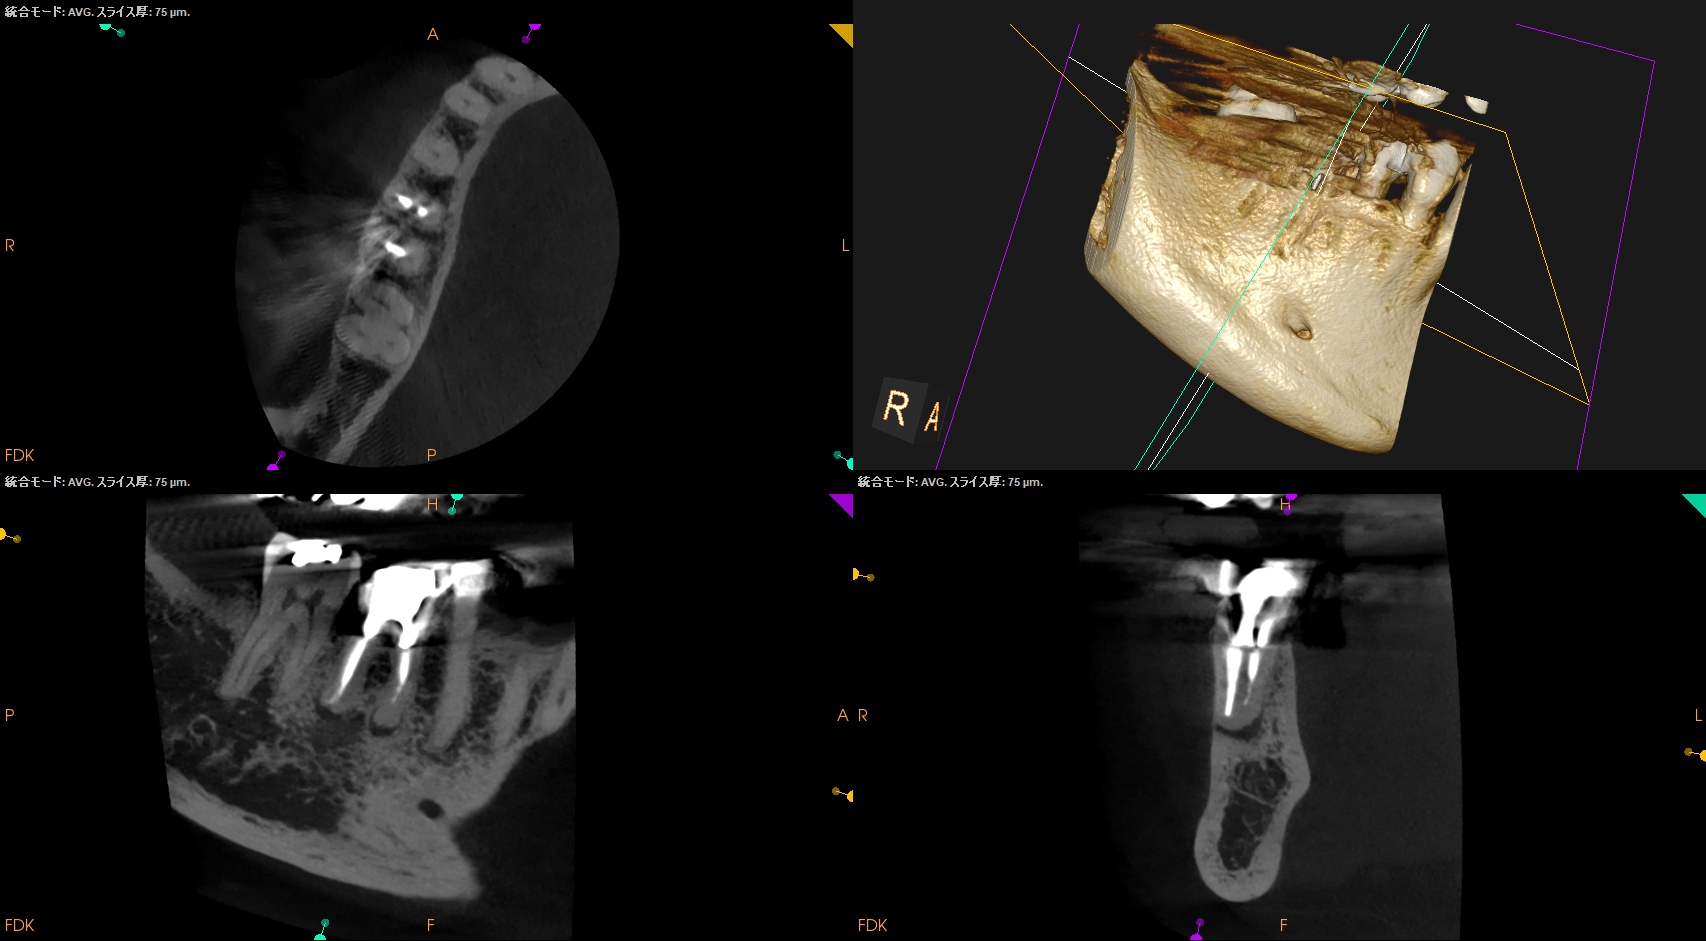

CBCT(2025.10.15)

#30 MB

#30 ML

#30 D